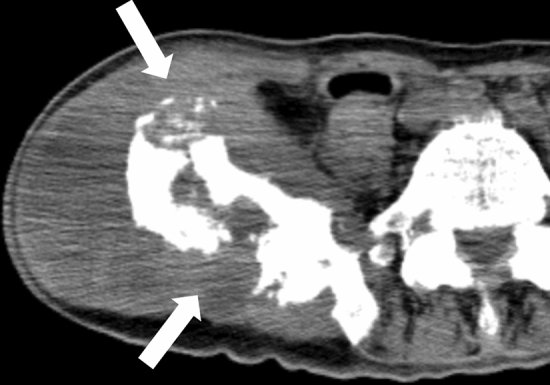

Fig. 3.

Representative CT images reflecting cardiopulmonary resuscitation. a extensive dilation of the gastrointestinal tract, gas in the intestinal wall and mesenteric vasculature. b the dilated medullary veins (arrows) near the lateral ventricles. c intraorganic and intravascular (broadly observed in the liver, abdominal aorta, vertebral body, and spinal canal) gas (scanned 10 h after death and also observed abdominal free air due to possible autolysis (unidentified bowel perforation by autopsy)). d gas in the arteries and veins in the brain (same case as Fig. 3c). e rib fractures in the anterior thoracic regions (arrowheads). f hemopericardium (arrows) due to cardiac rupture and sequel left hemothorax (black arrowheads) (also observed left rib fractures in the anterior thoracic regions (white arrowhead)). g right retroperitoneal hemorrhage (arrows) due to unknown cause confirmed by autopsy (same case as Fig. 3f)

Chest compression can easily cause rib fractures in the anterior and lateral thoracic regions (Fig. 3e) [50], and posterior rib fractures are usually considered inconsistent with chest compression. Chest compression can also complicate small pneumothorax, hemothorax, lung contusion, hemopericardium, and cardiac rupture (Fig. 3f) [51–53]. Intrapericardial and mediastinal hematomas may also occur. Owing to chest compression, sternal fractures can sometimes occur, and subcutaneous pre-sternal hematoma is sometimes observed following the use of a mechanical chest compression device [54]. Using mechanical chest compression devices can also result in unusual fractures of the mid-thoracic spine [55]. Abdominal hemorrhages, including peri-hepatic, peri-splenic, and retroperitoneal, are potential complications from chest compression attempts (Fig. 3g) [54, 56]. These findings can be explained when there is no other reason for antemortem pathology.